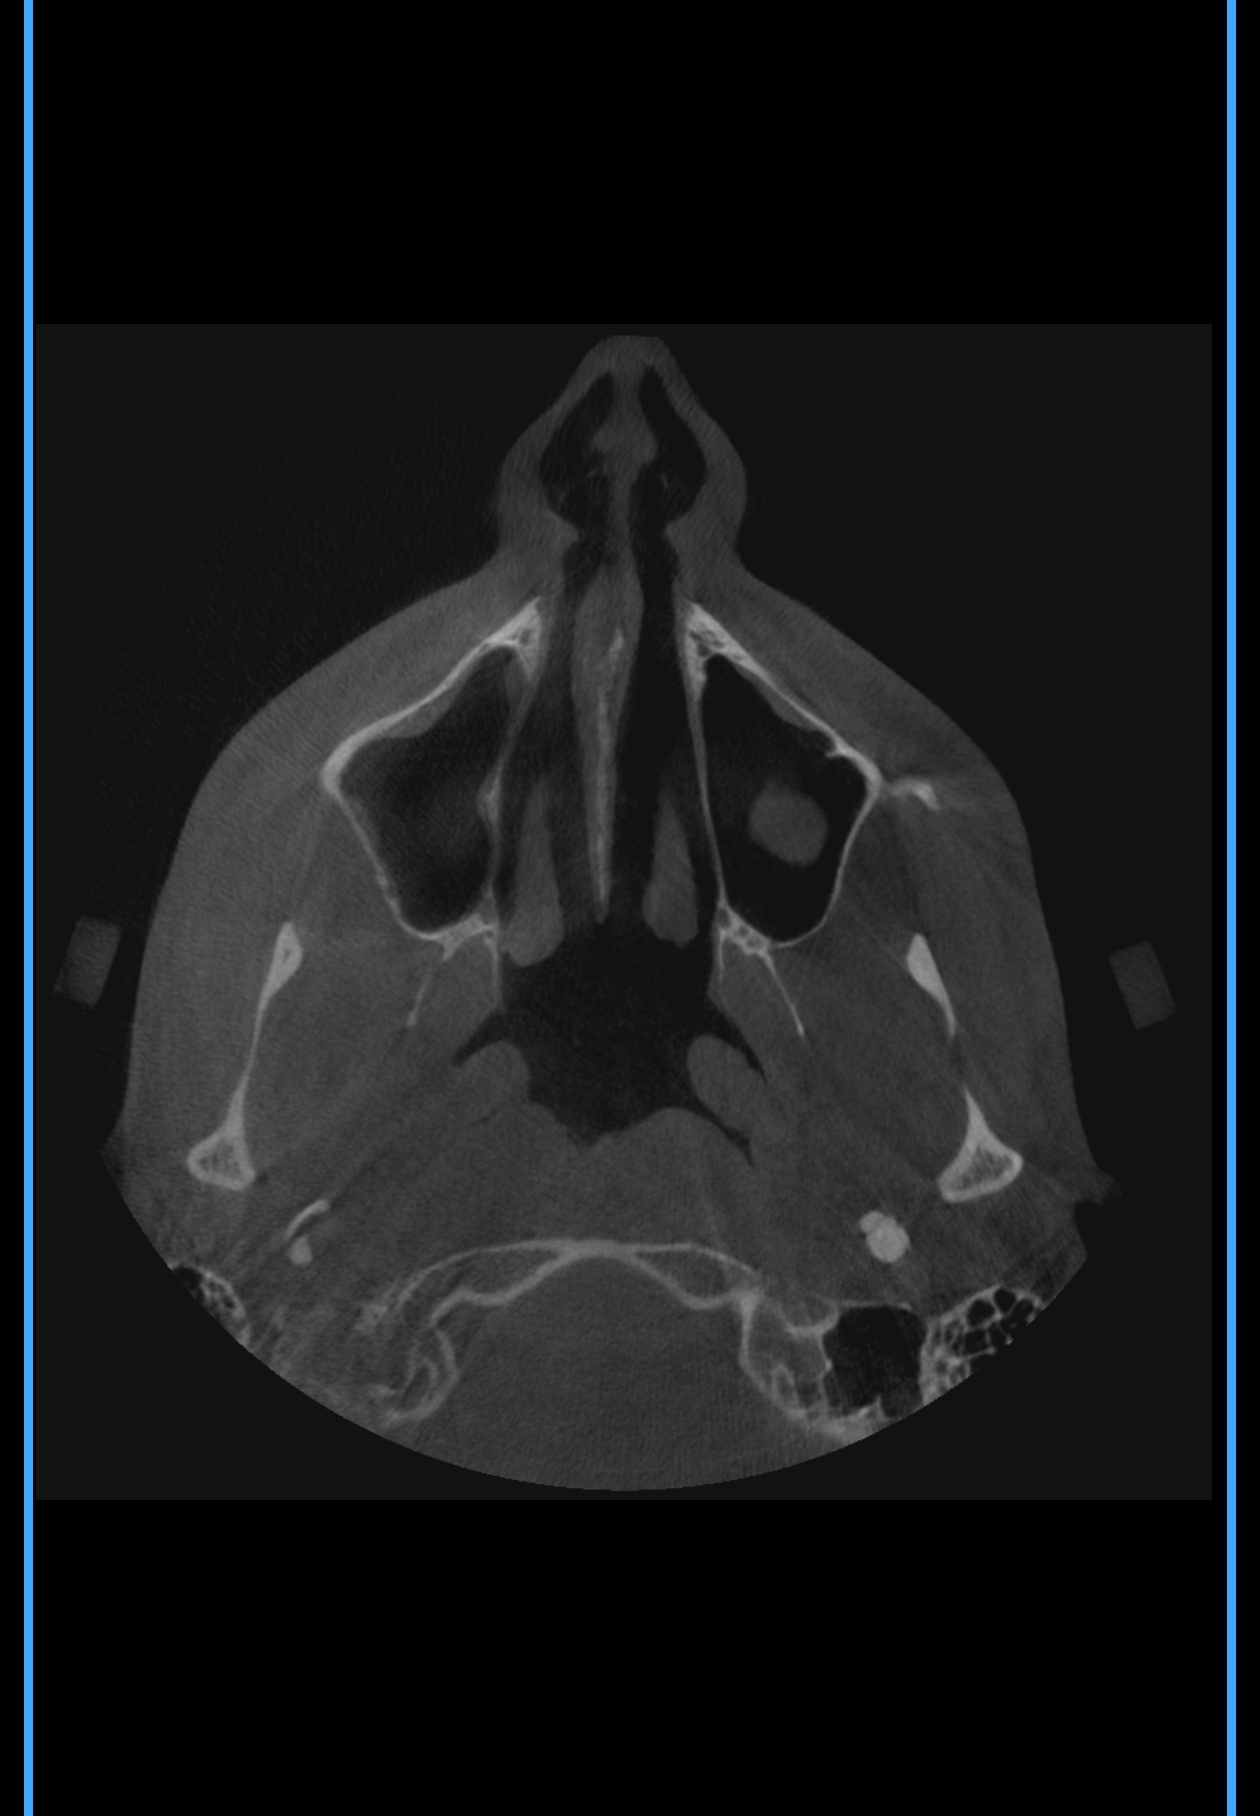

Тут же нужно выпрямлять носовые каналы или как это называется ? А то есть подозрение, что нудно будто бы всегда заложен и я чутка гундошу (когда слышу себя на записи)